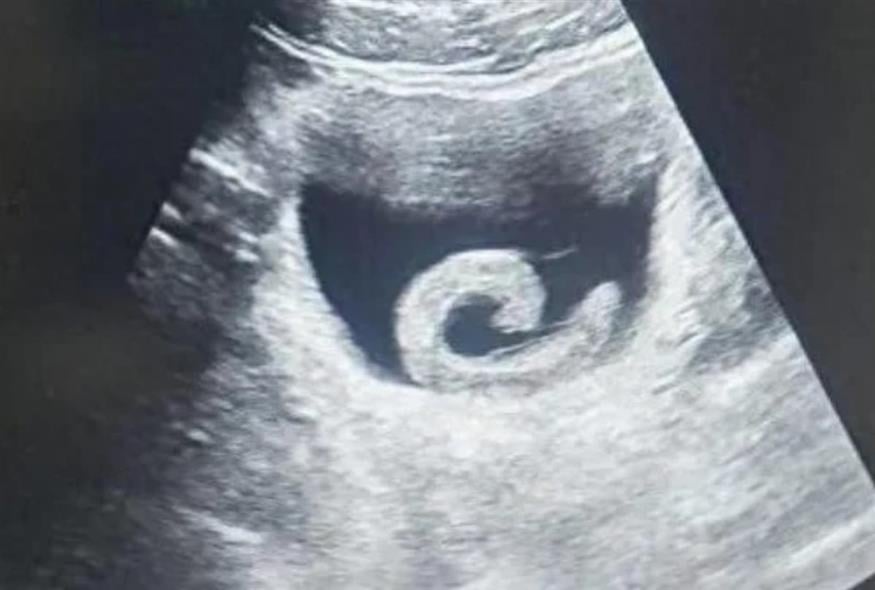

Το - λογικά απορημένο - ασπόνδυλο έφραξε την ουρήθρα με πρώτο αποτέλεσμα, ο Ζενγκ να μην μπορεί να ουρήσει και να νιώθει έντονη δυσφορία. Δεν έμεινε ομως εκεί. Προχώρησε και έφτασε μέχρι την ουροδόχο κύστη του, προσκολλήθηκε εκεί και άρχισε να απελευθερώνει ιρουδίνη (ένα ισχυρό αντιπηκτικό).

Ο 23χρονος άρχισε να διπλώνεται στα δύο από τους πόνους λόγω κυρίως της αδυναμίας να ουρήσει και πήγε εσπευσμένα στο νοσοκομείο, όπου περιέγραψε στους γιατρούς τι είχε κάνει. Με δεδομένο ότι κινδύνευε η ζωή του, τον έβαλαν αμέσως στο χειρουργείο και κατάφεραν να του αφαιρέσουν τη βδέλλα, επιτρέποντάς του να ανακουφιστεί...